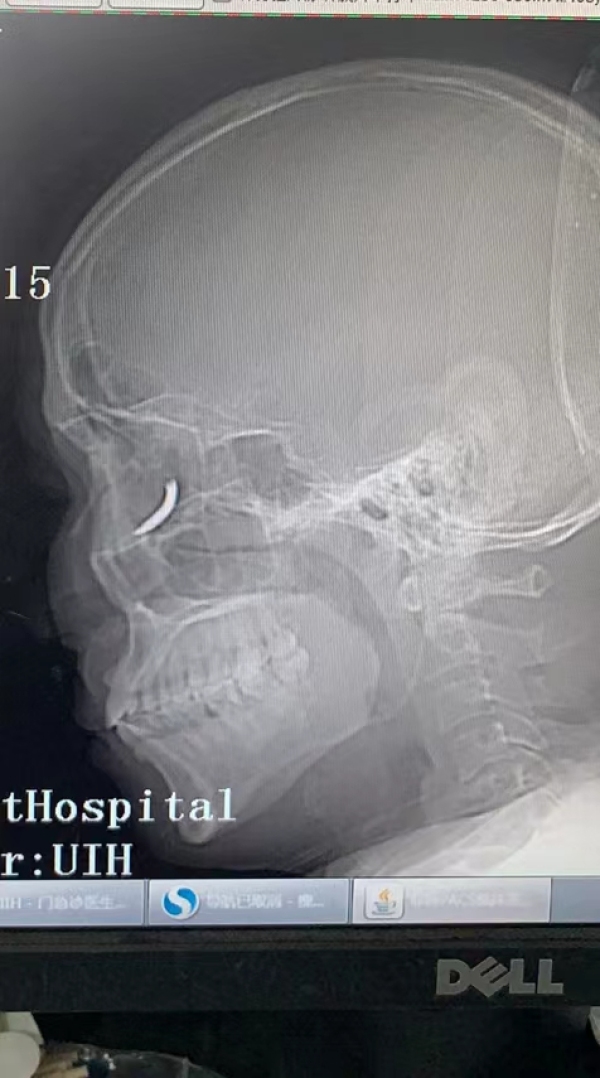

但是三天来王师傅一直感觉头晕不适,他去溧水当地医院就诊,拍了X光片后,竟然发现自己眼眶内有一个铁钉样的异物。

专家们发现这枚铁钉不偏不倚正好扎进病人的眼眶里,但是眼眶内解剖结构复杂,要在尽可能保护正常组织结构的情况下完成探查并取除铁钉,手术难度较大。

范伟杰与赵贵阳反复讨论后,制定了详细周密的手术方案,最终以局麻下、眼袋美容切口进入,顺利取出铁钉。整台手术耗时半小时,手术过程中没有损伤到眼球壁和视神经,但医生发现因为铁钉的侵入,视网膜周边有出血,所以做了视网膜光凝。术后视力1.0,面部看不出瘢痕。王师傅的眼球终于安全保住了。